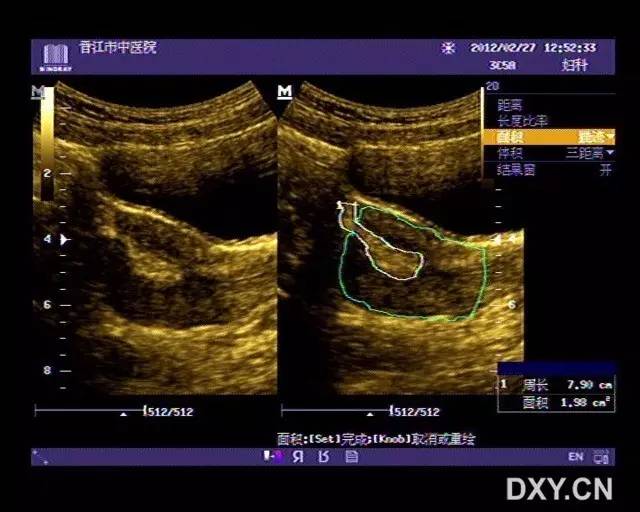

子宫穿孔的超声诊断

超声典型病例子宫穿孔

子宫穿孔彩超下表现

子宫穿孔彩超图